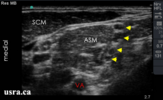

So when you are looking at 3-5 black circles in the interscalene groove, how do you differentiate which ones are C5, C6, C7 vs. multiples coming off the same root? For example how do we know in the picture below that we are not looking at C5, C6, C6, C7 (or any other anatomical variant).

So when you are looking at 3-5 black circles in the interscalene groove, how do you differentiate which ones are C5, C6, C7 vs. multiples coming off the same root? For example how do we know in the picture below that we are not looking at C5, C6, C6, C7 (or any other anatomical variant).